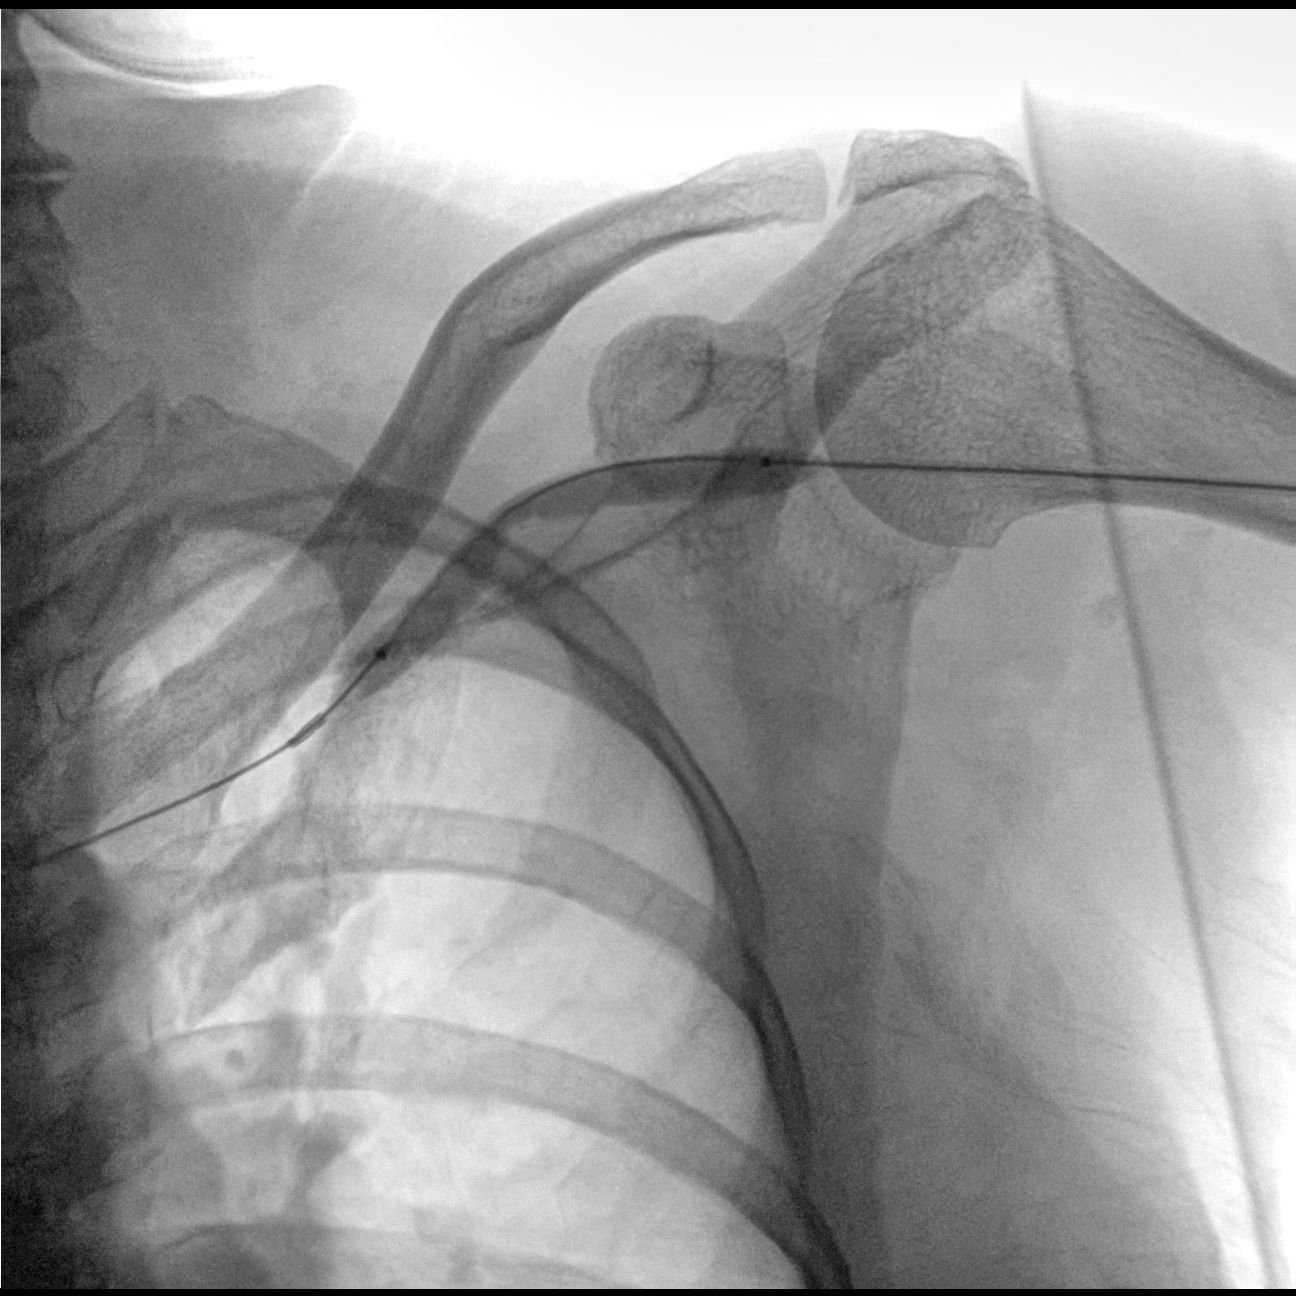

- Функция субтракционной ангиографии (DSA);

В качестве приемника используется динамический плоскопанельный детектор 26×26 см с разрешающей способностью более 4,5 пар.лин./мм., позволяющий визуализировать мельчайшие объекты с высоким разрешением. За счет применения динамического плоскопанельного детектора отсутствует эффект дисторсии, что повышает диагностическую значимость исследований. Большой диапазон выбора значений кадров с секунду при импульсной рентгеноскопии позволяет значительно снизить лучшею нагрузку, при этом при необходимости возможно проводить исследования с частотой до 30 кадров в секунду.